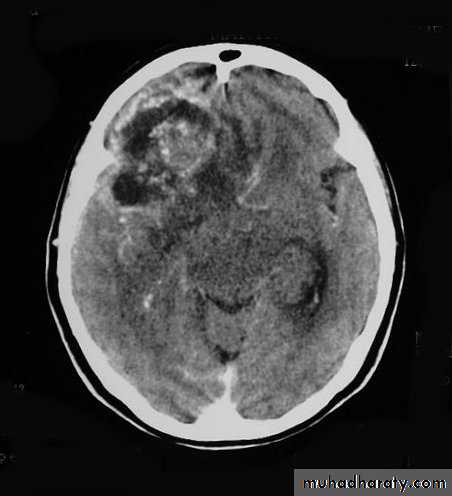

Metastatic Brain Tumours

• Constitute 15% of intracranial tumours.

• The commonest sites of origin are the lung (40%) and breast (10-30%), in addition to melanoma (5-15%), kidney and colon.

• In 15% of cases, a primary source is never found.

• On CT, they only show well with intravenous contrast.

• Steroids may help reduce peritumour oedema.

• Surgery may be appropriate for an isolated metastasis.

CSF shunt used for lesions causing Hydrocephalus.

• Radiotherapy can be used for multiple metastases.